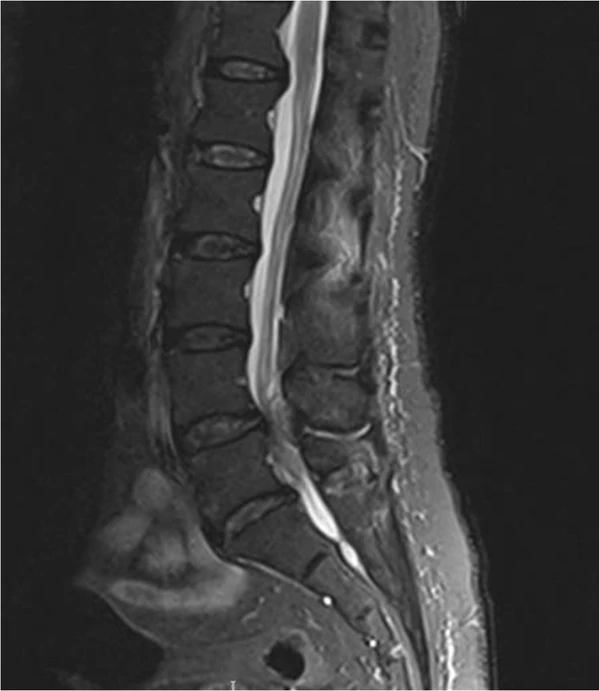

Диагноз первоначально предполагается клинически на основании анамнеза и физикального осмотра и обычно подтверждается МРТ или КТ, в зависимости от возможности их проведения. Сканирование мочевого пузыря и потеря чувствительности катетера также могут быть использованы для оценки дисфункции мочевого пузыря при подозрении на синдром конского хвоста и могут помочь в диагностике до проведения МРТ[6].